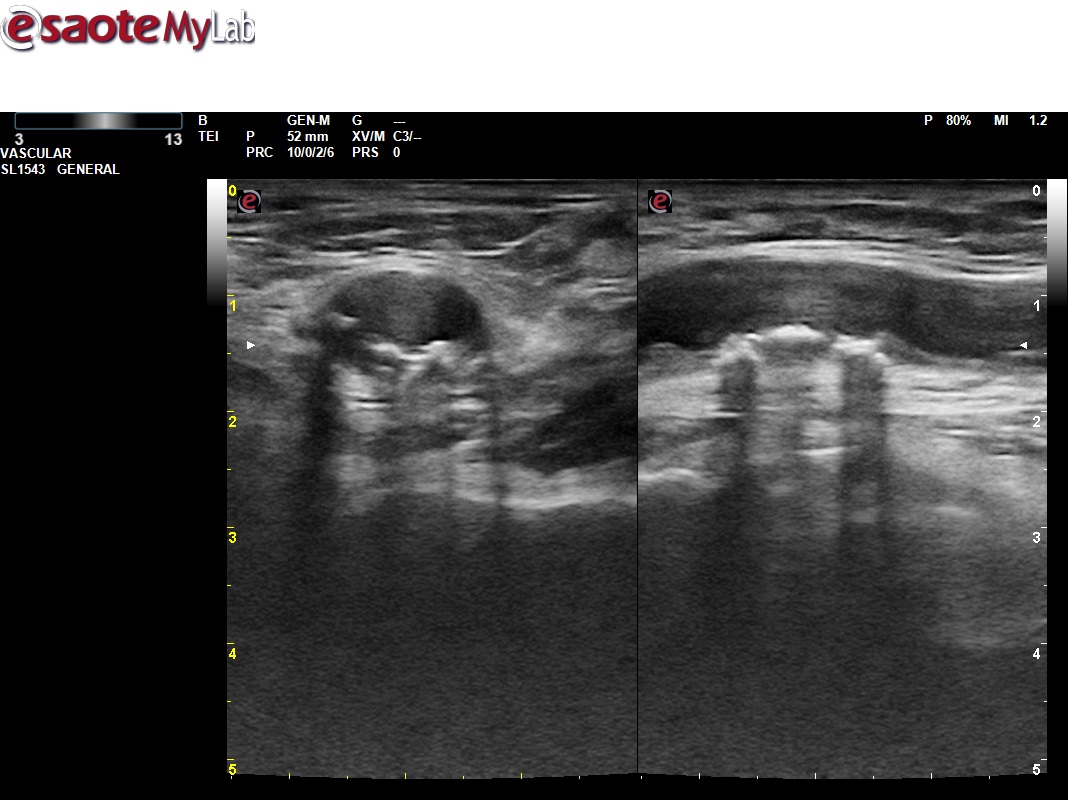

Mostramos el uso de la ecografía en el contexto de una actividad comunitaria, como es la celebración de puertas abiertas de un centro de salud por sus 25 años de apertura. Dentro de las múltiples actividades desarrolladas, se realiza una mesa de valoración de Riesgo cardiovascular (RCV) participando todos los estamentos, desde la unidad de atención al usuario (UAU) captando pacientes, como enfermería para valoración de factores de RCV, medicina para establecer SCORE, objetivos de control y puesto ecográfico para reestratificar a pacientes con bajo/moderado riesgo aplicando el protocolo VASUS de la SEMI (Sociedad Española de Medicina Interna).

La experiencia ha fortalecido el trabajo interdisciplinar, otorgando reconocimiento a todos los niveles asistenciales y visibilizando nuestra actividad clínica. Asimismo, ha estrechado el vínculo con los pacientes y dinamizado la incorporación de la ecografía en la práctica diaria. Además de manera destacada, en un elevado porcentaje de participantes se identificaron placas ateroscleróticas, modificando así sus objetivos de control y poniendo de manifiesto la gran utilidad de la técnica. Estos hallazgos subrayan la necesidad de abordar el infradiagnóstico de la aterosclerosis y refuerzan la conveniencia de integrar sistemáticamente la ecografía en la Atención Primaria.